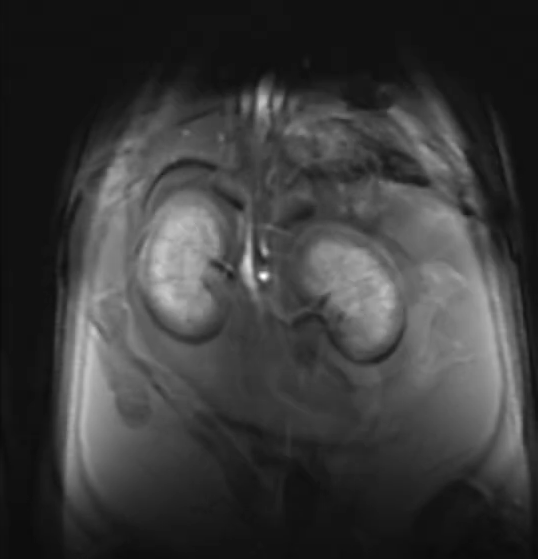

Le Centre abrite le seul appareil d’IRM pour petits animaux à grand champ de la région d’Ottawa (système Discovery MR901 de 7,0 Tesla d’Agilent Technologies / General Electric).

Le Centre abrite le seul appareil d’IRM pour petits animaux à grand champ de la région d’Ottawa (système Discovery MR901 de 7,0 Tesla d’Agilent Technologies / General Electric). Il n’y a qu’environ 10 machines de ce type dans tout le Canada qui offrent une occasion unique de tirer parti de cette ressource et d’obtenir un avantage dans le contenu de votre manuscrit.

Le système d’IRM est équipé d’un aimant supraconducteur à alésage horizontal de 7,0 T et 310 mm de diamètre, interfacé avec la plateforme Signa HDx de General Electric. Le système offre des capacités de recherche préclinique en IRM de haute qualité et robustes avec une variété de contrastes d’imagerie et d’évaluations quantitatives. CIPC fournit un service pour répondre à un large éventail de besoins des chercheurs, de l’imagerie d’animaux vivants aux recherches d’échantillons, la caractérisation d’agents de contraste à la recherche de matériaux et de plantes.

L’imagerie est réalisée à l’aide d’un puissant système de gradient de 300 mT/m (30 Gauss/cm) (diamètre intérieur de 210 mm) équipé d’une capacité de cale d’ordre 2. Une large gamme d’antennes de radiofréquence (bobines) sont disponibles, allant des antennes de corp aux antennes de réception dédiées et activement découplées pour le cerveau de souris et de rats. Des systèmes de surveillance physiologique et de manipulation des animaux sont également disponibles. Le spectromètre IRM est équipé de capacités X-nuclei.